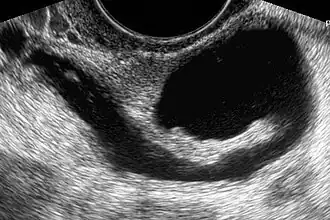

A histerossonossalpingografia é um procedimento médico realizado para avaliar a saúde do útero e das trompas de falópio de uma mulher.[1] Ele é frequentemente usado para diagnosticar possíveis problemas, como obstruções nas trompas de falópio ou anormalidades uterinas.

Primeiro, um espéculo é colocado na vagina, o que permite localizar o pescoço. Em seguida, é desinfetado com um anti-séptico (betadina vaginal ou cloherxidina). Uma cânula é introduzida através do orifício cervical na cavidade uterina e o espéculo é removido. Subsequentemente, uma sonda de ultrassom transvaginal é introduzida na vagina. Através da cânula dentro do útero, é injetada uma solução ou gel visível ao ultrassom. Esta solução pode variar, utilizando soro fisiológico estéril, meio salino ou Echovist. Finalmente, a passagem da referida solução ou gel da cavidade uterina para as trompas é visualizada por ultrassom, bem como é verificada a passagem do referido gel ou solução das trompas para a cavidade abdominal. No caso de obstrução tubária, essa passagem de líquido para a cavidade abdominal não podia ser visualizada.

Principalmente, as imagens ultrassonográficas obtidas por uma histerossonossalpingografia podem mostrar anomalias uterinas ou tubárias, tanto do ponto de vista morfológico quanto fisiológico.[5]